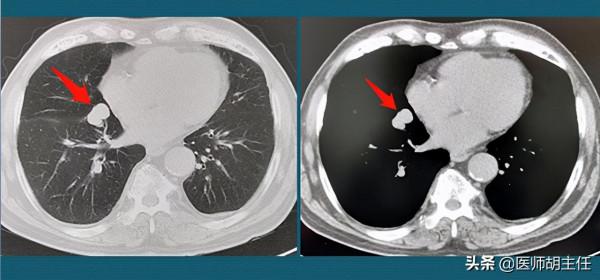

醫生讓陳女士做了肺部CT,發現了肺部增生結節,直徑10mm,算是比較大的結節了。但是結節形態規整,邊界清楚,內部質地均勻,周圍無磨玻璃樣,無毛刺。

暫無惡性結節特徵,但是由於結節直徑較大,惡性病變的機率增高,也不容忽視。醫生為了進一步確診是否是良性結節,讓陳女士做了血常規檢查,發現白細胞和中性粒細胞增多,有炎症感染的症狀,初步判定為炎症結節。

果然,檢查情況不容樂觀!之前呈現良好趨勢的結節,三個月後,結節反而長了2mm。可以說,按這種增長速度,已經可以基本肯定是結節惡化,並且以癌細胞的身份進行擴散了。再看結節形態,形狀不規則,呈現邊緣短毛刺,與周圍肺部黏膜牽扯,形成胸膜凹陷徵,屬於初級浸潤型惡性結節。